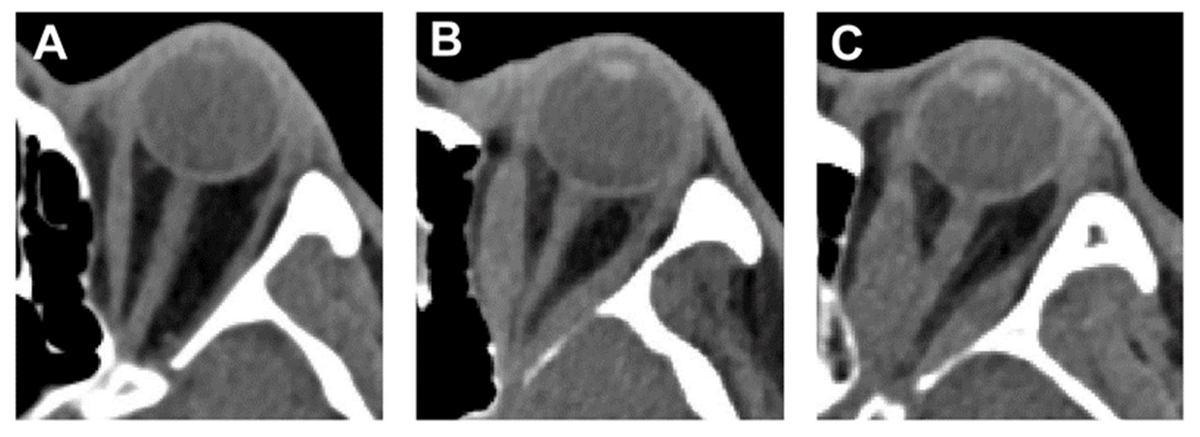

(3) the presence of a visual field defect lower than 5.0 decibels. The representative CT images of TED-NM, TED-IM-Non-DON, and TED-IM-DON are shown in the following figures.

The computed tomography (CT) images of patients with thyroid eye disease (TED) with normal motility (TED-NM) (A), non-dysthyroid optic neuropathy (DON) in impaired motility (IM) group (TED-IM-Non-DON) (B), and TED-IM-DON (C).